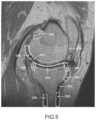

FIG.5 is a sagittal plane image slice of a femur and tibia depicting regions where good definition may be needed during automatic segmentation of the femur and tibia.

FIG.8 is a sagittal plane image slice depicting automatically generated slice curves of a femur and a tibia.